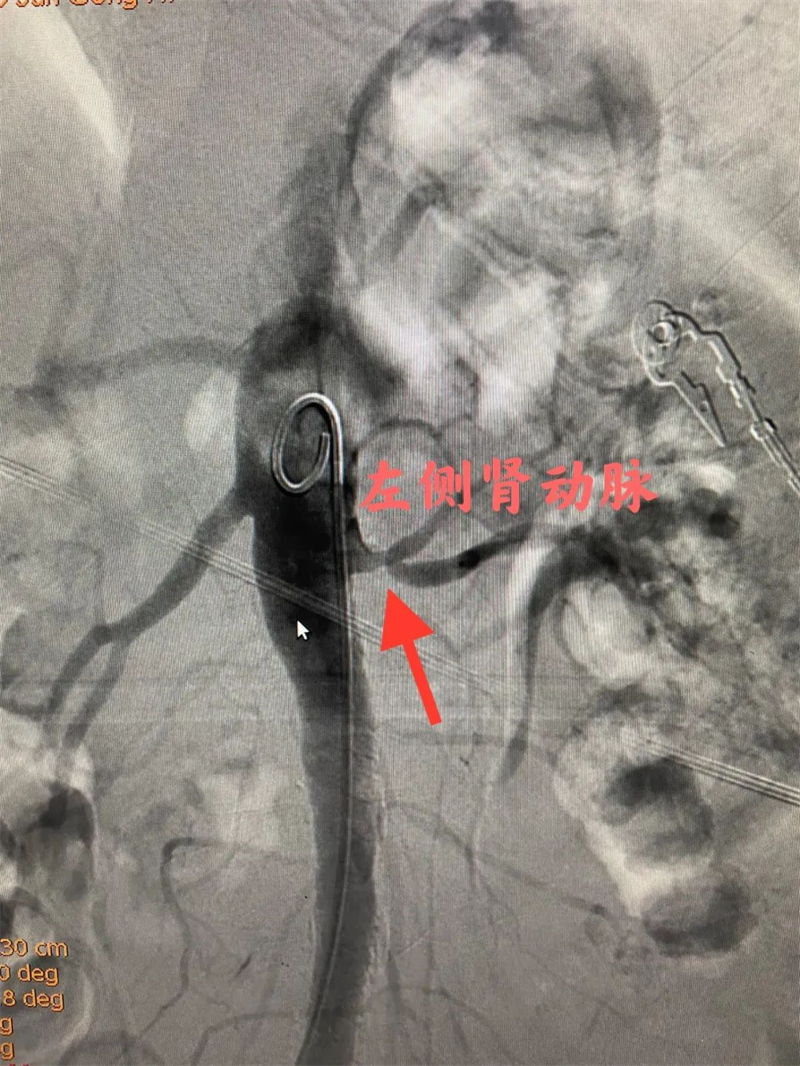

经过充分的准备后,心血管内二科及神经血管介入科团队通过股动脉穿刺,为患者顺利完成冠状动脉造影、肾动脉造影及左侧锁骨下动脉造影。冠状动脉造影结果提示患者前降支远段70%狭窄,确诊为冠状动脉粥样硬化性心脏病。肾动脉造影提示左侧肾动脉起始段中度狭窄,明确了肾动脉狭窄。左侧锁骨下动脉造影提示起始段次全闭塞。成功植入两枚支架,术后患者头晕缓解,左侧桡动脉搏动有力。